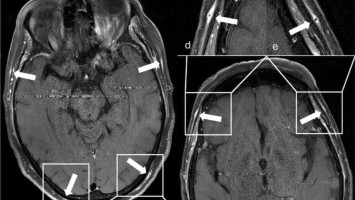

Schwannomatose bei Kindern und Jugendlichen: hohe Relevanz frühzeitiger Diagnostik

Die häufigste Form der Schwannomatose (SWN) ist die NF2 -bedingte SWN, die mit einer Inzidenz von 1:61.332 auftritt (Tab. 1 ). Früher wurde diese SWN-Form als Neurofibromatose Typ 2 (NF2) bezeichnet, und die genetische Ursache ist eine …

Titelbild Kongress Kompakt EULAR 2025/© Hintergrundbild: william87 / stock.adobe.com, Wunde wird mit Wundspray versorgt/© Ilja / Stock.adobe.com (Symbolbild mit Fotomodell), Kutane Arzneimittelreaktion/© Hötzenecker, W., Hautveränderungen an der rechten Wange/© M.V. Heppt, In Risikogebieten tragen circa 1–2 % der Zecken das FSME-Virus./© astendal / stock.adobe.com (Symbolbild mit Fotomodell), MRT-Aufnahmen der Kopfschwarte bei Riesenzellarteriitis/© Universitätsklinikum Würzburg, Fillerbehandlung im Gesicht eines Mannes/© Microgen / stock.adobe.com (Symbolbild mit Fotomodell), Neurofibromatose auf der Haut/© Alexander Schuh / Klinikum Fichtelgebirge, Wespen auf Stein/© merlion / Getty Images / iStock (Symbolbild), Eine Person raucht eine E-Zigarette/© vchalup / stock.adobe.com (Symbolbild mit Fotomodell), Mund mit herausgestreckter Zunge: Medikamenteninduzierte Xerostomie mit extrem trockener Mundschleimhaut/© F. Halling | Die junge Zahnmedizin (16)·3:26-31, Aknenarben/© Hautwerk, Konfokale optische Kohärenztomographie mit Line-Field-Technologie/© Deußing, M. et al. / all rights reserved Springer Medizin Verlag GmbH, Ex vivo konfokales Laserscanmikroskopiebild eines Morbus Bowen/© Grunewald S et al. / all rights reserved Springer Medizin Verlag GmbH, Zwei Injektionspens mit Semaglutid/© Kassandra / Stock.adobe.com, Immuncheckpointinhibitoren binden an Krebszelloberflächenproteine /© Juan Gärtner / stock.adobe.com, Morbus Castleman: Sonographie eines Lymphknotens/© Springer Medizin, Person kratzt sich am Arm/© 9nong / stock.adobe.com (Symbolbild mit Fotomodell), Arzt tastet Bein ab/© Stratocaster / Stock.adobe.com (Symbolbild mit Fotomodellen), Hämorrhagisches Erysipel am Unterschenkel/© Sunderkötter C et al. / all rights reserved Springer Medizin Verlag GmbH, Piks in Oberarm/© stalnyk / stock.adobe.com, Gewitter mit Blitzschlag/© solarseven / Getty images / iStock, Behandlung eines diabetischen Druckulkus/© Alexander Schuh, Eine Person, die sich juckt und kratzt/© Maria Fuchs / stock.adobe.com (Symbolbild mit Fotomodell), Die Leitlinien für Ärztinnen und Ärzte, Herpes Zoster am Rücken/© Mumemories / Getty Images / iStock (Symbolbild mit Fotomodell), Mann erhält einen CT-Scan /© Mark Kostich / stock.adobe.com (Symbolbild mit Fotomodell), DGIM Podcast-Reihe - Frailty/© (M) David L / peopleimages.com / Stock.adobe.com (Symbolbild mit Fotomodell)